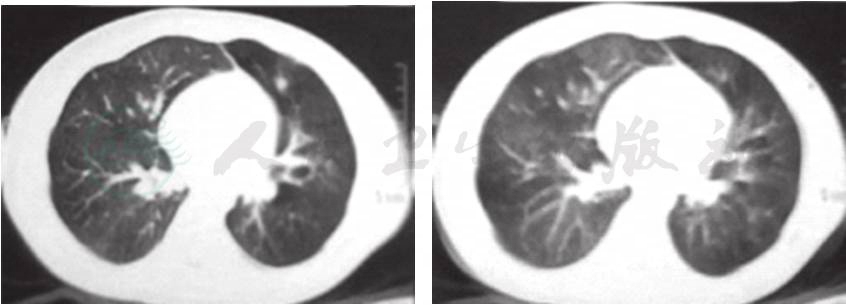

辅助检查:肺CT(当地医院,入院前2周)(图1):双肺透过度不均匀,双肺炎症,右肺部分实变。肺CT(笔者医院门诊)(图2A,图2B):双肺透过度不均匀,呈马赛克征改变,多叶段炎症,右肺部分实变,双肺散在肺气囊形成。

图1 入院前2周,当地医院肺CT